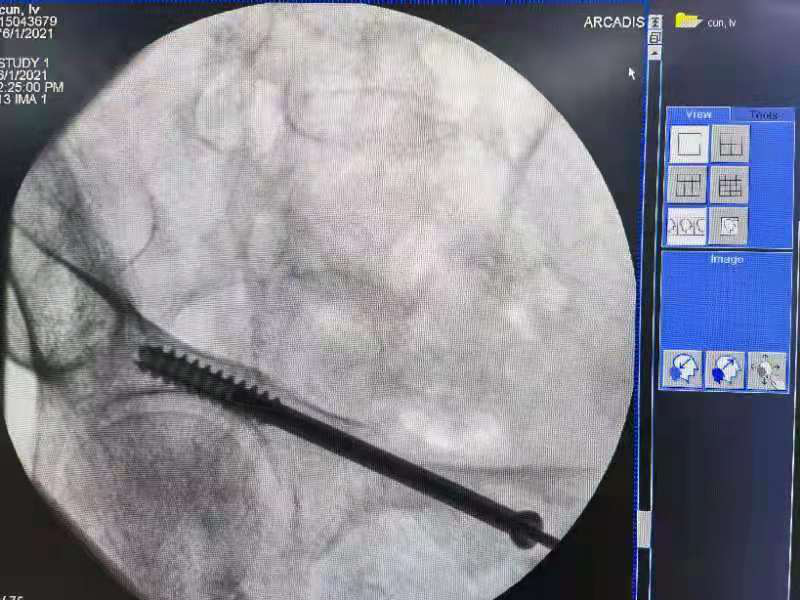

麻醉成功后,术中经过骨折的复位,在机器人导航下经皮成功置入螺钉固定,病人体表只有2厘米左右的手术切口。

◆术中

◆术中规划